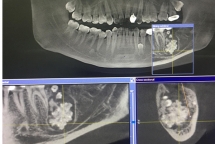

Nam thanh niên đi khám vì đau răng nhưng khi chụp X-quang, bác sĩ phát hiện bên dưới lợi lúc nhúc răng to nhỏ.